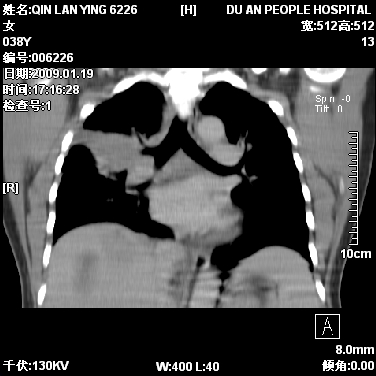

女,38岁,胸疼1个月。wbc:1万4

1)右肺中央型肺癌并右肺上叶阻塞性肺炎、节段性肺不张,纵隔淋巴结转移、右侧胸膜转移、肝脏转移。2)右侧胸腔少量积液。

1、右侧中央型肺癌并阻塞性肺不张,纵隔内、主动脉弓旁、右肺门淋巴结及肝脏转移可能性大,建议纤支镜进一步检查。

2、右侧胸腔积液。

本病例有几个容易诊断的地方:1、右肺上叶前段支气管闭塞,肺不张。2、淋巴结明显肿大。3、肝脏多个类圆形低密度影呈“牛眼征”改变,高度提示转移。

从影像学角度分析      右肺上叶中央型肺癌,并阻塞性不张、肺炎,纵隔淋巴结、膈顶淋巴结转移。

肝内两个大小不等低密度结节,内可见更低密度影,首先考虑肝内转移瘤,但联想到患者wbc1万4,建议楼主还是做个增强比较明确,除外肝脓肿的可能。